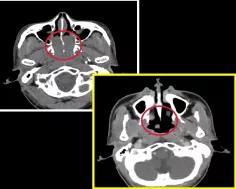

2、某鼻咽癌患者放疗前后对比

左图是治疗前,红色圆圈内是患者鼻咽部的肿瘤,右图是经过放射治疗之后,红色圆圈圈住的肿瘤团块已经几乎消失了。